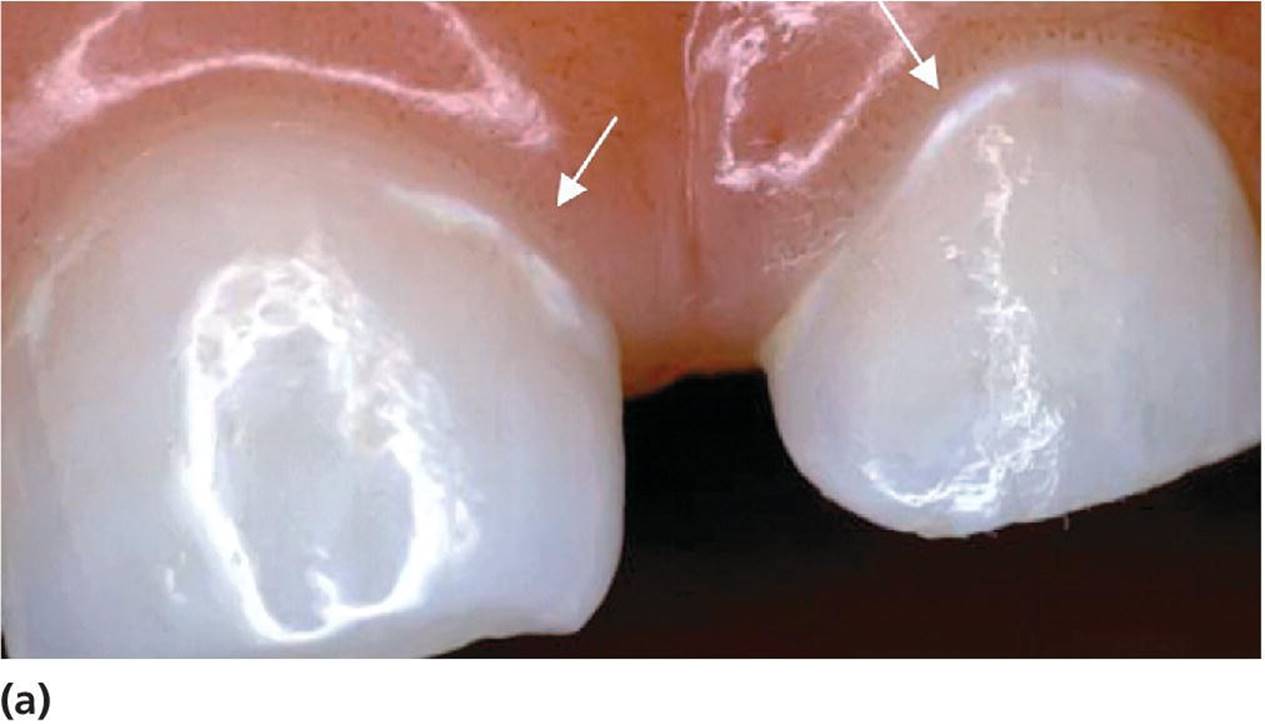

Assessment of lesion activity is as important as lesion detection. Criteria for active and inactive caries lesions slightly modified after Nyvad et al. [7] and Ekstrand et al. [8] are presented in Box 12.3. Figure 12.3illustrates active and arrested lesions.

Figure 12.3 Active and inactive/arrested caries lesions. Upper row shows initial (noncavitated lesions) and the lower row shows cavitated lesions. (a) Active noncavitated lesions close to the gingival line on the buccal surfaces of primary upper incisors in a 2‐year‐old. There is loss of luster and the lesions are rough on probing. (b) Arrested noncavitated lesions on the buccal surfaces of primary upper incisors in a 4‐year‐old. The lesions are situated at a distance from the gingival line, and are shiny and hard on probing. (c) Active cavitated lesion in a primary lower second molar in a 5‐year‐old. The dentin is soft on probing and the cavity borders are blunt and irregular. (d) Inactive/arrested cavitated lesion in a primary lower first molar in a 7‐year‐old. The dentin is brownish‐black, hard on probing, and the cavity borders are sharp and regular.

Free smooth surfaces

The buccal and lingual aspects of teeth are easily examined, and it is easier to disclose small changes in surface color and texture of early caries lesions on these surfaces compared to “inaccessible” areas on approximal surfaces or in pits and fissures. The active lesion on free smooth surfaces is usually located near the gingival margin. It is whitish and rough in texture (Figure 12.3a). In contrast, a typical inactive lesion is often seen in primary incisors at a distance from the gingival margin when the tooth is fully erupted, is hard on probing, and the lesion may be shiny (Figure 12.3b).